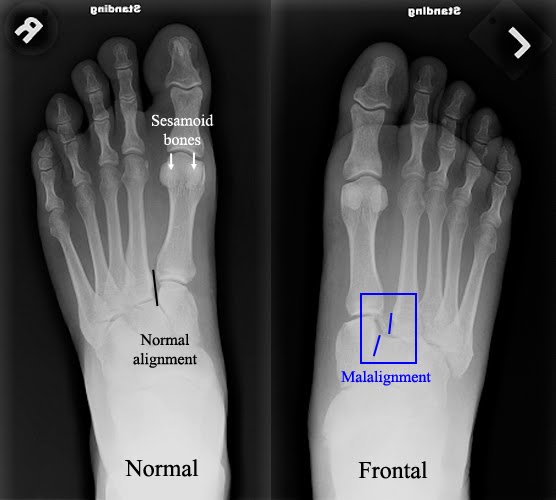

Pin on X-rays